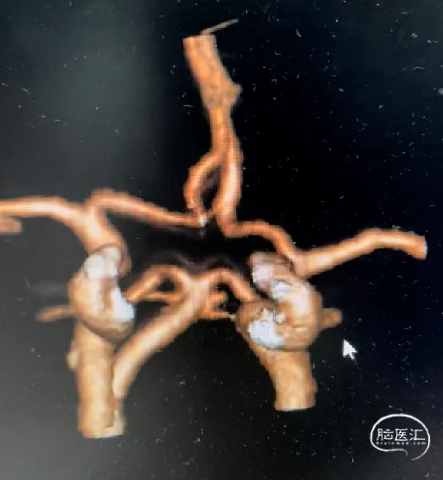

术前影像